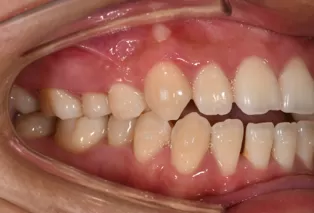

Intraoral photos